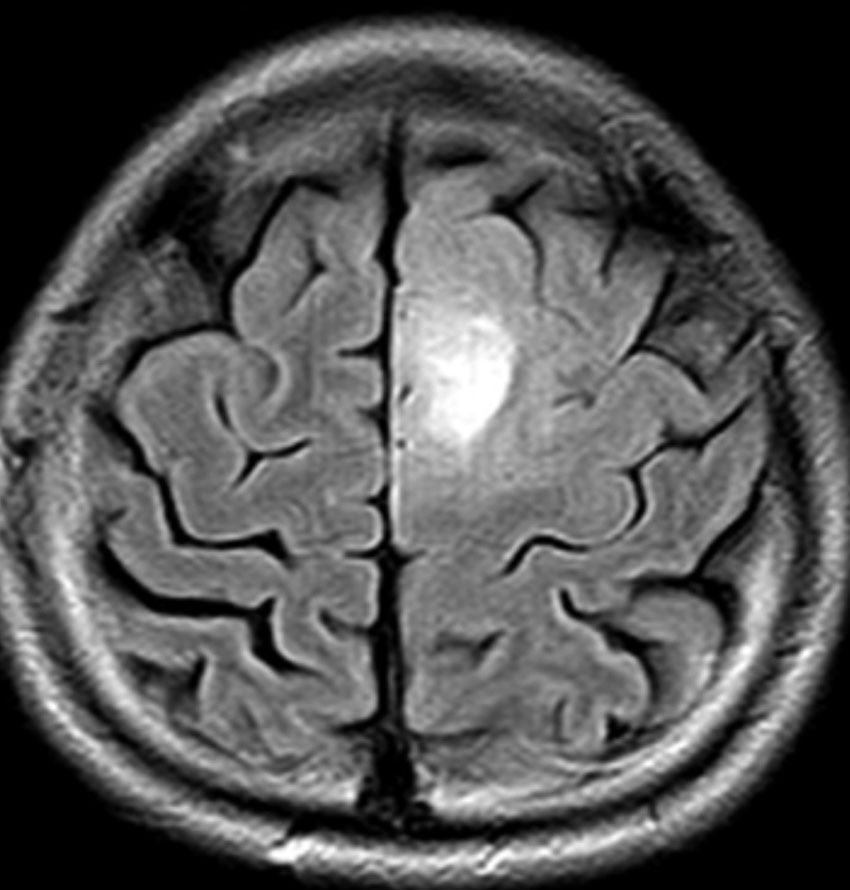

MRIでみえる腫瘍の領域を腫瘍体積 (GTV)といいます

これは退形成性星細胞腫グレード3のフレア画像と言います。白く見える部分が腫瘍なのですが,どこまでが腫瘍なのかMRIでもわかりにくいものです

オレンジの色がGTVではっきり腫瘍と断定できるところです

グリオーマはMRIでみえる以上に広がっているので,腫瘍の周囲を十分に囲む領域を照射します,それを臨床的標的体積 (CTV)といいます